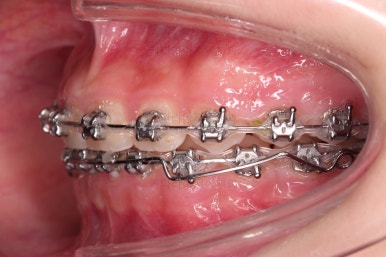

우선 윗니에만 교정장치를 부착했습니다.

성장치료라더니 교정치료? 하실 수 있지만 윗니를 가지런하게 해준 이유는 아래턱을 앞으로 성장시켜줄려니 윗니 앞니가 옥니처럼 가로막고 있어서 아래턱이 앞으로 나올래야 나올 수 없는 상황이었어요.

그래서 앞니의 각도를 먼저 개선해주기로 했죠.

일반적인 교정장치이긴 하지만 그 목적이 달랐던 거에요.

앞니의 각도가 앞으로 살아난 것이 보이실 거에요.

자연스레 과개교합 경향도 개선되어 어금니로 물렸을 때 아래 앞니가 점점 보이기 시작해요.